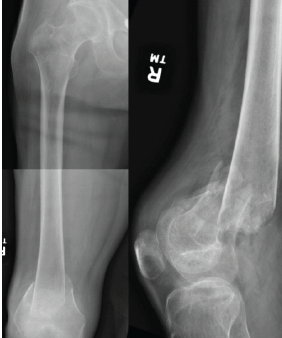

Treatment of Bilateral Distal Femoral Shaft Fractures in a Paraplegic Patient with Intramedullary Nailing: A Case Report

Ernesto S Quinto, Jr. , Brendan J Liakos , William L Pistel

………………………………p.229-233